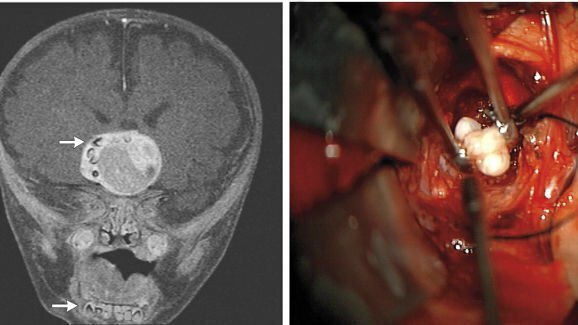

BALTIMORE, EUA: Nos EUA, neurocirurgiões descobriram dentes múltiplos completamente formados dentro da massa de um tumor que estava crescendo no centro do cérebro de um bebê de 4 meses. O garotinho foi inicialmente atendido numa clínica em Baltimore após uma consulta de rotina pediátrica devido ao aumento na circunferência da cabeça.

De acordo com o relatório do caso, publicado on-line em 27 de fevereiro no New England Journal of Medicine, foi feita uma ressonância magnética na cabeça da criança após ter dado entrada no Centro Infantil Johns Hopkins, que revelou uma massa (4.1 cm × 4.0 cm × 3.5 cm) parecida com hipófise. Os médicos também identificaram estruturas próximas à massa similares aos dentes da mandíbula.

Durante a cirurgia de remoção do tumor, os cirurgiões descobriram dentes dentro da massa que foram identificados como craniofaringiomas adamantinomatosos no exame patológico. Tais tumores de crescimento lento surgem da bolsa de Rathke, um precursor embrionário da glândula pituitária anterior, e consistem do epitélio escamoso estratificado queratinizado, e podem ser císticos. Os cistos possuem um fluído amarelo viscoso contendo cristais de colesterol. Os médicos explicaram que craniofaringiomas adamantinomatosos histológicamente parecem muito com tumores odontogênicos.

A cirurgia foi realizada há um ano. De acordo com o relatório do caso, desde então o paciente tem necessitado de desvio para higroma subdural bilateral e reposição hormonal de adrenal e tiroide. Entretanto, ele está progredindo bem e faz ressonância magnética regularmente, disseram os médicos.